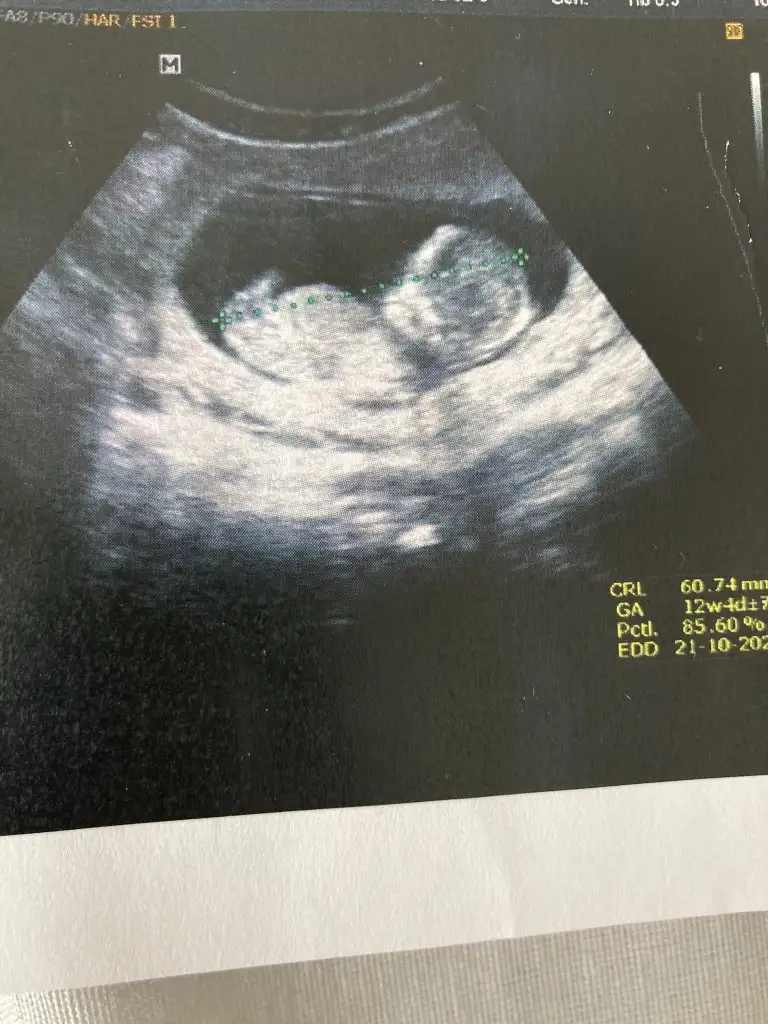

Benim bebeğime de bakar mısınız 12+4 günlük burada doktor cinsiyetini göremedii sizce nedir

Ikra meyra merhabalar sanırım nub belli değil ama şansımı denemek istedim 11+2 yiz bugün tahmininiz nedir